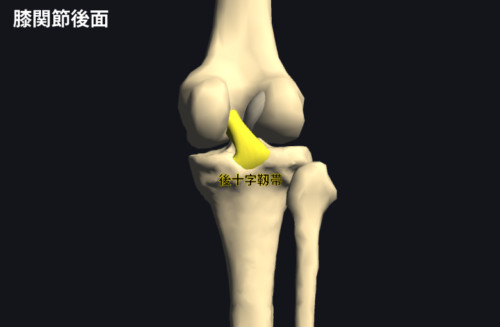

後十字靭帯は「大腿骨の内側顆」から「脛骨の顆間隆起後方」に付着する関節内靱帯で、脛骨の後方への偏移を制動します。

膝関節内には2本の靱帯があり、それらが交差して十字に見えることから前方を前十字靭帯、後方を後十字靭帯と名付けられました。

後十字靭帯(PCL)は長さが30–40mm前後、幅が約1cm前後であり、前十字靭帯(ACL)よりも太くて頑丈です。